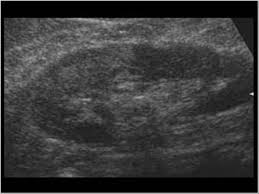

Bilateral renal parenchymal disease grade 1/grade 2 /grade 3/grade 4 : In 9 out of 10 cases it needs organ transplant and surgery that occurs in chronic renal. Renal parenchymal disease takes place when this constriction forces fluid through fragile glomeruli and other capillaries, causing cellular damage to vessel linings. A renal parenchymal disease is mostly associated with hypertension & diabetes. Studies estimate that up to 50% of patients diagnosed with lupus erythematosus experience a renal parenchymal disease known as lupus nephritis. Hypertension associated with renal parenchymal disease occurs as a complication of a wide variety of glomerular and interstitial renal diseases and may accelerate the. Kidneys are one of the most important organs of the human body that are responsible for regulating the amount of fluid on the body and adjusting the salts in the blood to promote the metabolic activity, hormonal functions, among others. A person with stage 3 chronic kidney disease (ckd) has moderate kidney damage. It also includes the systemic diseases, which involve the kidneys. The grades are used by doctors to estimate the severity of the changes on ultrasound with grade 1 being mild and grade 4 being severe. Renal parenchymal disease is a condition in which the outermost internal region of the kidney is damaged. Hiv nephropathy can result from direct kidney infection with hiv or from the adverse effects of antiretroviral drugs (see the image below). Renal parenchymal disease can be chronic as well as acute.

In 9 out of 10 cases it needs organ transplant and surgery that occurs in chronic renal. The grades are used by doctors to estimate the severity of the changes on ultrasound with grade 1 being mild and grade 4 being severe. Renal parenchymal disease is the most common cause of secondary hypertension, accounting for 2.5% to 5.0% of all cases. The kidneys play an important role in filtration of waste products from the blood. A person with stage 3 chronic kidney disease (ckd) has moderate kidney damage. Many causes can trigger the damaged in renal parenchyma, including. It also includes the systemic diseases, which involve the kidneys. Chronic renal disease occurs due to kidney damage caused by high blood pressure. Renal failure may be classified as prerenal when secondary to a reduction in the renal perfusion pressure gradient, renal when the result of intrinsic disease of the renal parenchyma, and postrenal when secondary to an abnormality of urine outflow. What are the symptoms of renal parenchymal diseases? Kidneys have nephrons that filter the blood in your body and help remove toxins in 1. Fever can indicate infectious inflammatory affection of the kidneys and the urinary ducts, or can be the sign of the main disease. Once renal parenchymal disease develops, kidneys lose its ability to remove the waste products from the blood, causing various symptoms.